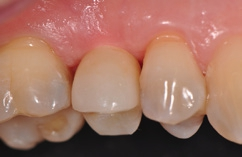

Definitive Eingliederung

Die mit dem Abutment verklebten Restaurationen konnten nun entnommen, Zementüberschüsse (Abb. 22) sicher entfernt und die Übergänge von Krone zu Abutment poliert werden. Für die definitive Eingliederung ist der für die Abutmentschraube vorgegebene Anzugstorque von 25 Ncm einzuhalten. Nach erneutem Auffüllen der Schraubenkanäle wiederum mit Teflonband wurden die Zugangskavitäten in ebenfalls üblicher Weise mit Komposit verschlossen. Das Ergebnis sind im vorliegenden Fall 2 metall- und zementfreie, verschraubte und reversible Einzelzahnrestaurationen (Abb. 23). Bei dem routinemäßig durchgeführten Follow-up 6 Monate nach Eingliederung zeigte sich eine an beiden Implantatpositionen reizlose Weichgewebssituation (Abb. 24a und b) und in den radiologischen Kontrollaufnahmen stabile periimplantäre Knochenverhältnisse (Abb. 25a und b).